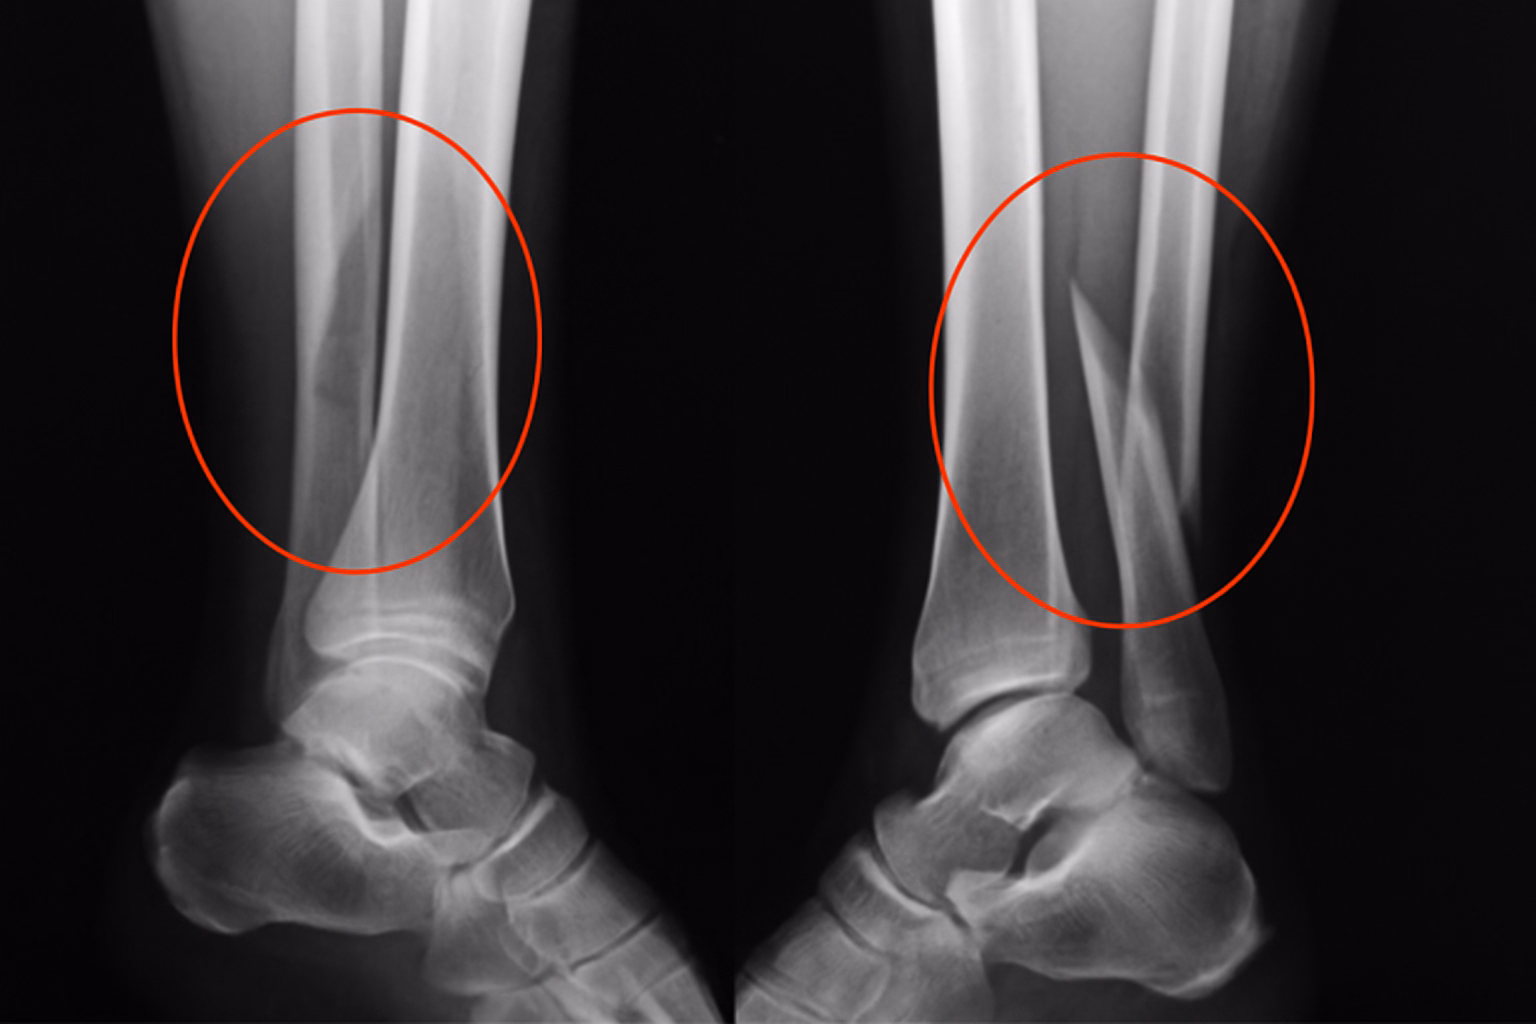

Exames de imagem (raio-x, tomografia, ressonância)

Os exames de imagem ajudam a entender o que está acontecendo com o osso e com as estruturas ao redor:

- Raio-X: mostra alinhamento, consolidação, presença de parafusos, placas ou haste e possíveis deformidades.

- Tomografia Computadorizada: avalia detalhes mais finos, como falhas de consolidação e desvios angulares.

- Ressonância Magnética: útil para investigar cartilagem, ligamentos, tendões e possíveis lesões associadas.